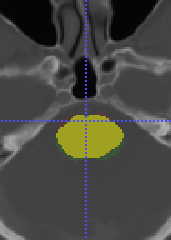

To model , we propose using a half-Gaussian distribution based on nodule size distribution because is correct if it is within the nodule area (center slice of as , and nodule size can be empirically estimated based on existing data) for nodule detection in Fig. 17(a). For lung lobe prediction , a logistic regression model is used based on relative value of nodule center after lung segmentation. That is

| (22) |

where is the associated weights with lobe location for logistic regression, feature , and is the total size of image after lung segmentation. In the experiments, we found the logistic regression converges quickly and is stable.